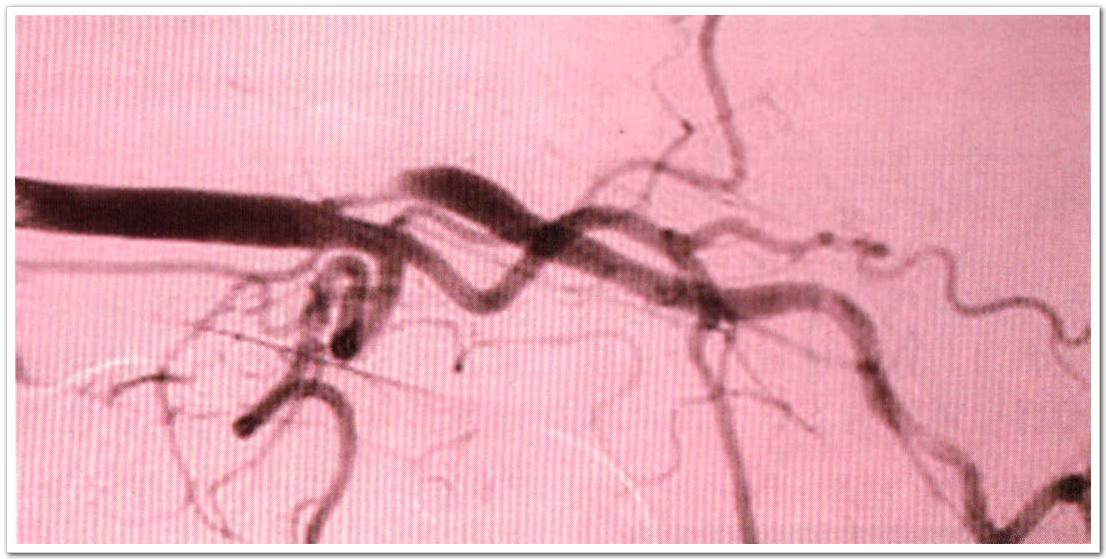

來自愛爾蘭國家兒童中心神經(jīng)內(nèi)科的McCabe等人在此多中心觀察性研究中,受試者為頸動脈狹窄≥50%的患者,受試者被分為無癥狀組(31例),early phase癥狀組(46例,缺血性卒中或TIA發(fā)作后4周之內(nèi))和late phase癥狀組(35例,缺恤性卒中或TIA發(fā)作后3個月以上),在late phase癥狀組中,23例患者已經(jīng)接收了頸動脈介入手術(shù),稱為late phase介入組。對比無癥狀組、early phase癥狀組、late phase癥狀組患者的VWF:Ag及VWF:Ag II水平。對有癥狀的患者進(jìn)行隨訪評估。TCD監(jiān)測將患者分為MES陽性組或陰性組。

實(shí)驗(yàn)結(jié)果表明:VWF:Ag II水平,early phase癥狀組患者(12.81g/ml;P<0.001)、late phase癥狀組患者(10.61g/ml;P=0.01)和late phase介人組患者(10.61g/ml;P=0.038) 與無癥狀組相比較(8.9g/ml)均明顯增高。VWF:Ag水平,在有癥狀患者隨訪期間,從發(fā)病早期到晚期逐漸下降(P=0.048)。early phase癥狀組而且MES陰性的患者比無癥狀組而且MES陰性的患者VWF:Ag II水平增高(13.3vs9.0lg/ml;P<0001)。

此研究結(jié)論:癥狀性頸動脈狹窄患者與無癥狀性頸動脈狹窄患者相比,內(nèi)皮細(xì)胞活性增強(qiáng);early phase癥狀組而且MES陰性患者與無癥狀的MES陰性患者相比內(nèi)皮細(xì)胞活性增強(qiáng);而在有癥狀的患者中內(nèi)皮細(xì)胞活性隨著時(shí)間延長而而下降。在頸動脈狹窄患者中,VWF:Ag II水平比VWF:Ag更敏感。MES檢測結(jié)合腦血管內(nèi)皮標(biāo)志物在預(yù)測頸動脈狹窄卒中風(fēng)險(xiǎn)中的潛在價(jià)值值得進(jìn)一步研究。